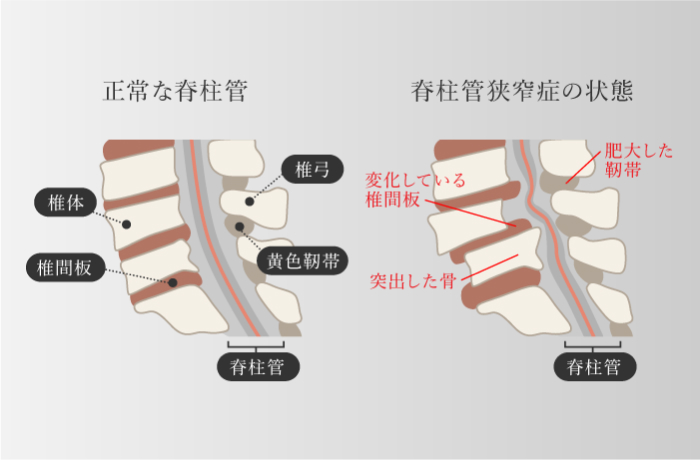

脊柱管狭窄症(神経根型/馬尾形)

-

柱管内部の変性が原因

- 腰部神経組織周囲が変性や肥厚することにより神経を圧迫する

- 間欠性跛行(閉塞性動脈硬化症との鑑別)

診断基準(日本整形外科学会ガイドライン)

- 殿部から下肢の疼痛やしびれを有する

- 殿部から下肢の疼痛やしびれは立位や歩行の持続によって出現あるいは増悪し、前屈や座位保持で軽快する

- 歩行で増悪する腰痛は単独であれば除外する

- MRIなどの画像で脊柱管や椎間孔の変性狭窄状態が確認され、臨床所見を説明できる

※4つすべて満たすと脊柱管狭窄症と診断されます。

※脊柱管狭窄症と診断されたが、上記の4項目のうち1つでも当てはまらないものがある方は、改善できる可能性があります。